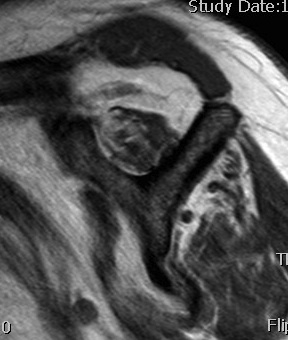

MRI predictors of reparability

- 60 patients with large and massive tears

- irreparability associated with retraction to or beyond glenoid

- irreparability associated with tangent sign / advanced fatty infiltration / superior migration humeral head

- 120 patients with large and massive tears

- irreparability associated with modified grade III Patte (retraction to medial 5th humeral head)

- associated with 94% chance or irreparability

- irreparability also associated with reduce acromiohumeral distal / superior migration humeral head

Examples of rotator cuff tears that are likeley irreparable